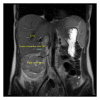

A 22-year-old female presented with back pain and was discovered to have a right-sided abdominal mass. Computed tomography (CT) scan revealed a 9 cm enhancing right upper pole renal mass with suspicion for tumor thrombus into the right renal vein and possibly the inferior vena cava (IVC). Magnetic resonance imaging (MRI) confirmed tumor thrombus into the inferior vena cava approximately 3 cm below the hepatic venous confluence. Open right radical nephrectomy with inferior vena cava thrombectomy was performed with removal of right kidney and tumor thrombus en bloc. Pathology revealed malignant epithelioid angiomyolipoma (EAML or PEComa). Epithelioid angiomyolipoma is a rare tumor of mesenchymal tissue that has the potential for local invasion and disease progression. Diagnosis of EAML was confirmed by pathology and immunohistochemistry. She was referred to medical oncology for discussion of surveillance versus potential adjuvant therapy and ultimately opted for close surveillance.